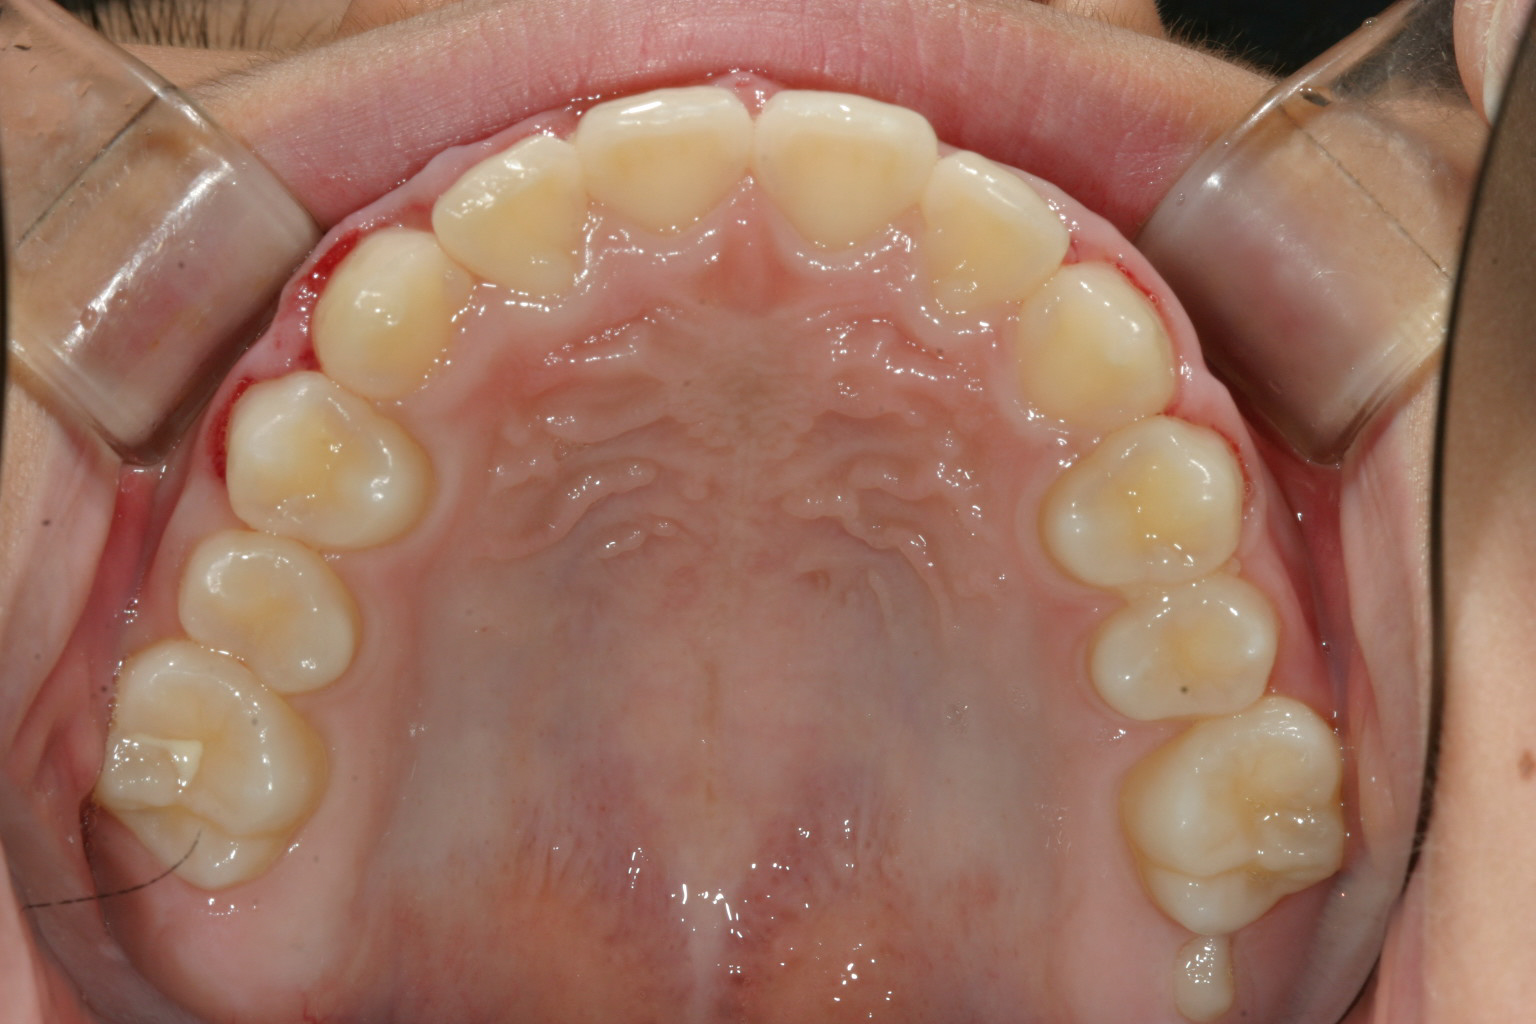

下顎は綺麗なアーチですね~